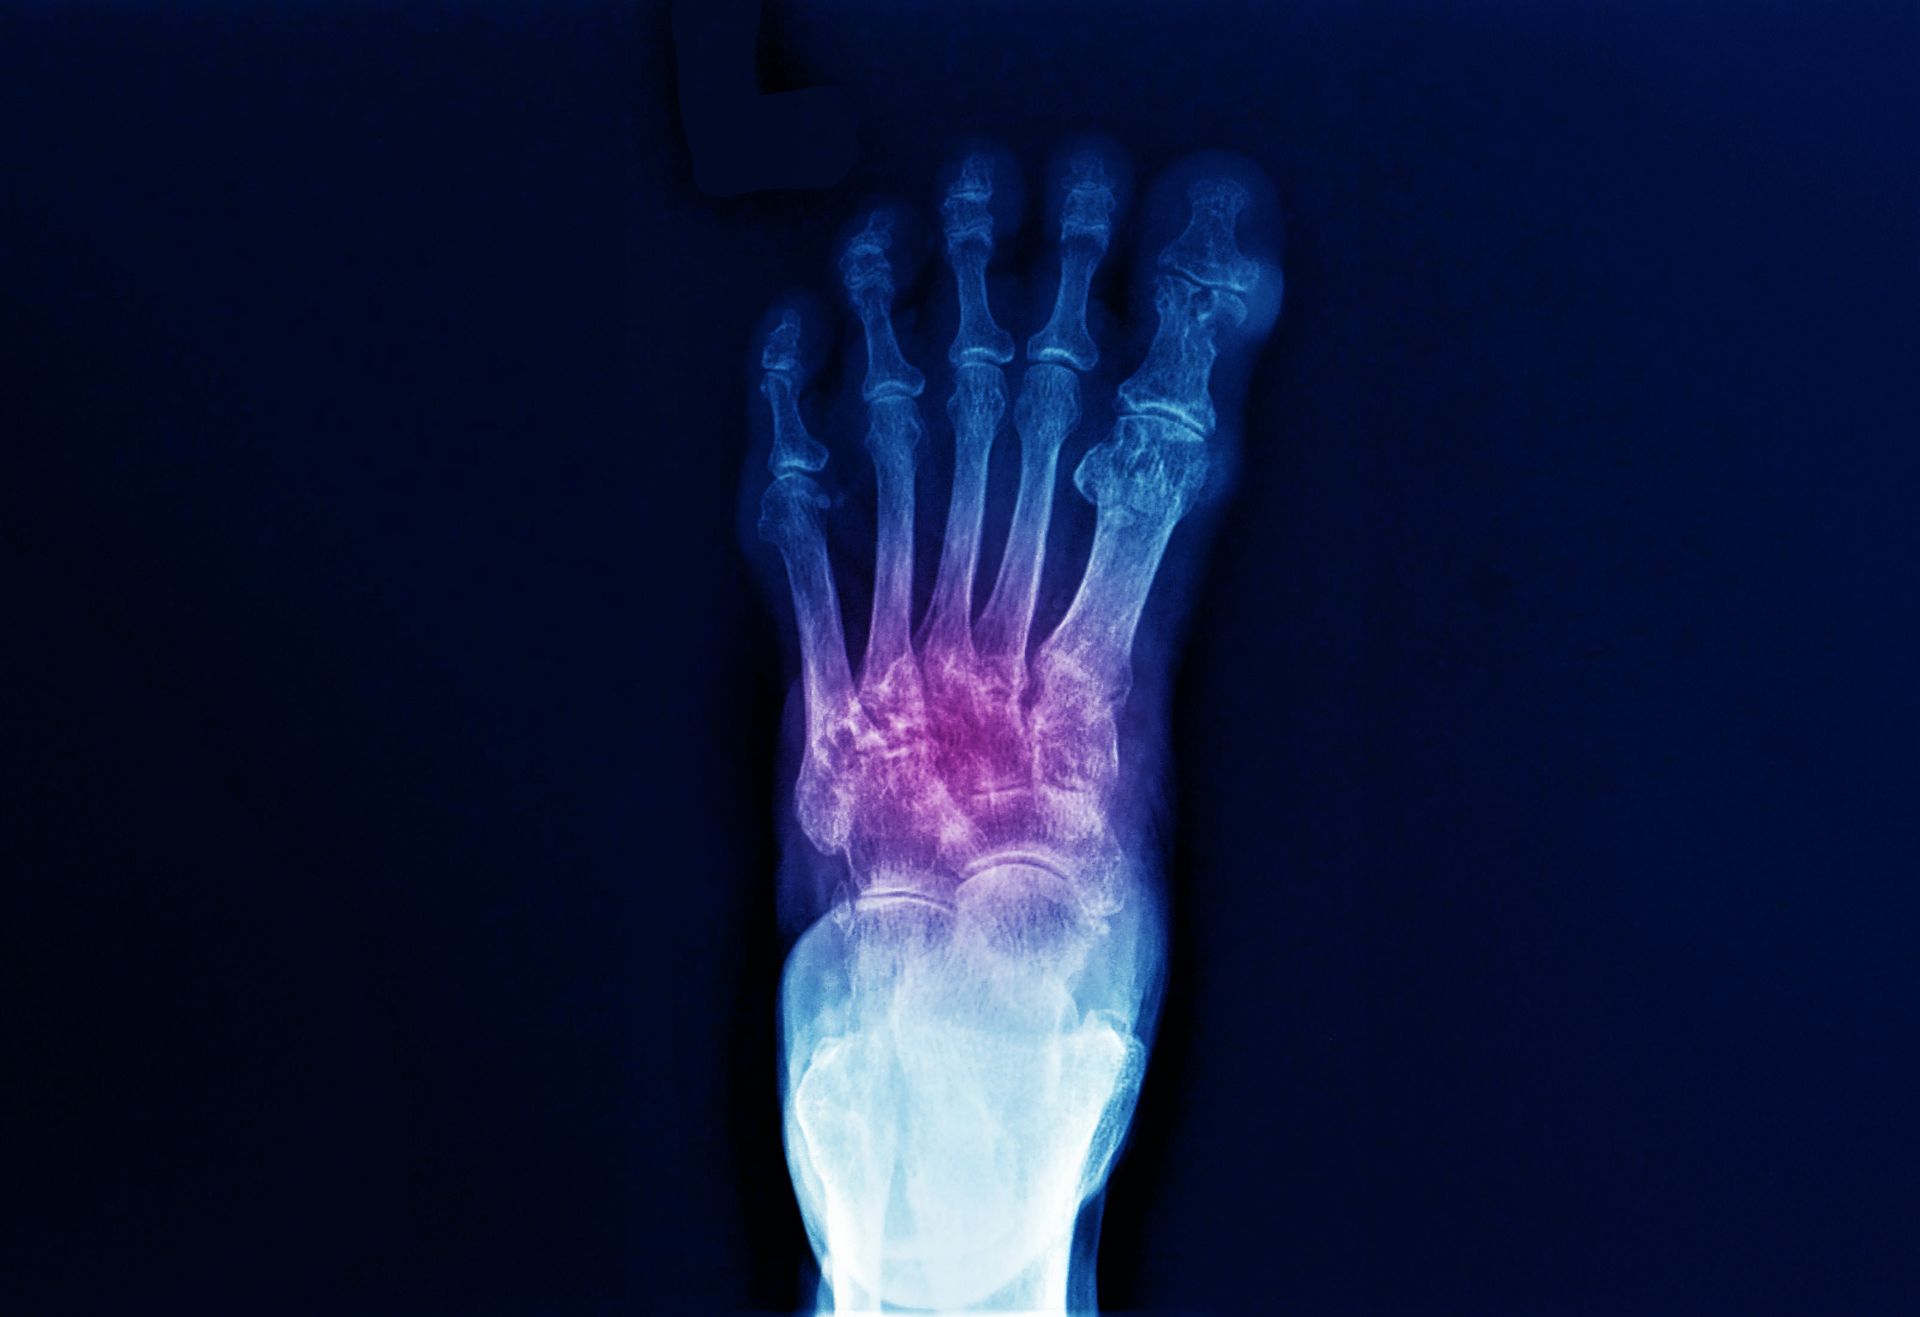

Podiatric medicine focuses on diagnosing and treating conditions of the foot, ankle, and related structures of the leg. Podiatrists perform thorough examinations, make accurate diagnoses, and provide treatments that may include medication, therapeutic exercises, custom orthotics, surgical procedures when needed, and guidance on footwear, prevention, and lifestyle habits to support long-term lower extremity health and overall well-being.